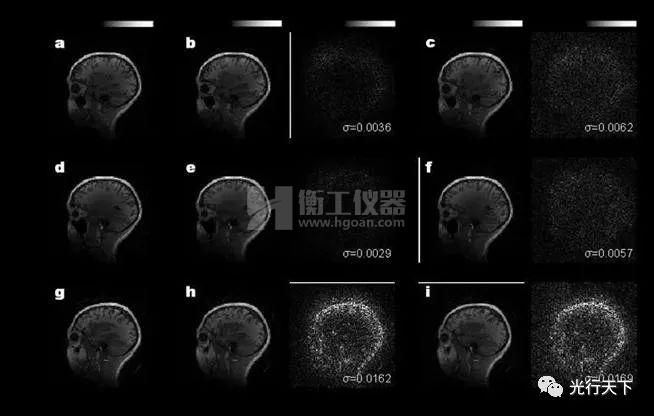

光學(xué)相干點(diǎn)積核芯片重構(gòu)結(jié)果與計(jì)算機(jī)結(jié)果的對(duì)比

本研究中,鄒衛(wèi)文教授團(tuán)隊(duì)利用醫(yī)學(xué)圖像重構(gòu)任務(wù)作為驗(yàn)證,在芯片上成功地運(yùn)行了AUTOMAP(用于通用圖像重構(gòu))神經(jīng)網(wǎng)絡(luò)模型,圖像重構(gòu)的質(zhì)量接近了32位計(jì)算機(jī)的理想水平。該工作不僅推動(dòng)光學(xué)神經(jīng)網(wǎng)絡(luò)研究領(lǐng)域攻克實(shí)際應(yīng)用難題,更為下一代智能計(jì)算技術(shù)提供了新思路。后續(xù)進(jìn)一步提高芯片的器件集成規(guī)模,有望實(shí)現(xiàn)更高速、更低功耗的光學(xué)神經(jīng)網(wǎng)絡(luò)處理器,緩解智能算力需求劇增與傳統(tǒng)硬件算力受限的矛盾。 該工作由上海交通大學(xué)、北京大學(xué)與中科院半導(dǎo)體所合作完成。上海交通大學(xué)為第一完成單位,博士研究生徐紹夫?yàn)榈谝蛔髡?,鄒衛(wèi)文教授為通訊作者。